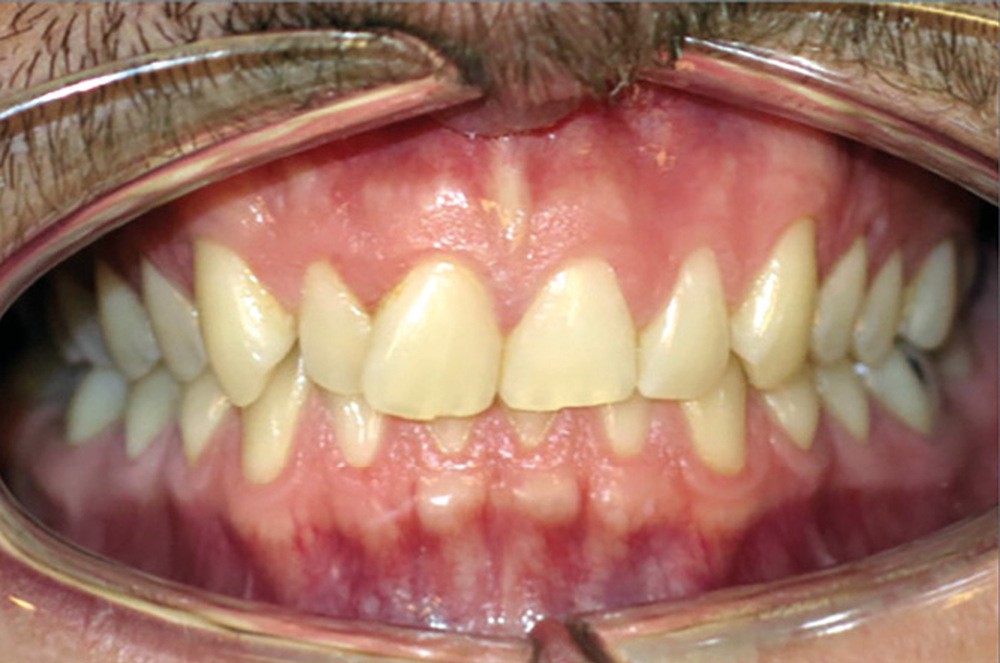

Examen endobuccal (fig. 2a-e)

L’arcade maxillaire est asymétrique, en hémi-lyre droite. Elle présente une mésio-position du secteur 1 en lien avec un encombrement antérieur estimé à 4 mm, se traduisant par une palato-position de la 12 et une rotation de la 11. On observe également des mésio-rotations des premières molaires et une palato-version incisive. L’arcade mandibulaire est ellipsoïde et présente un léger encombrement incisif (1 mm).

Concernant les relations occlusales, on observe une classe II complète subdivision droite. Le surplomb est absent et le recouvrement augmenté, estimé à 4 mm, a provoqué une usure des bords libres de 11 et 21 par attrition. Dans la dimension transversale, on constate une endoalvéolie maxillaire, ainsi qu’une concordance des médianes incisives entre elles, mais toutes deux déviées à droite par rapport au plan sagittal médian.